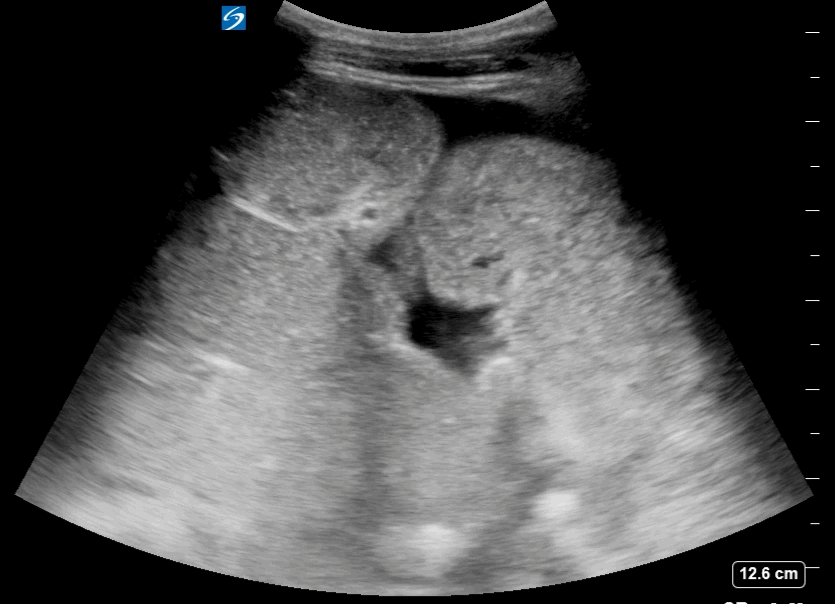

Free Fluid Around the Intestinal loops